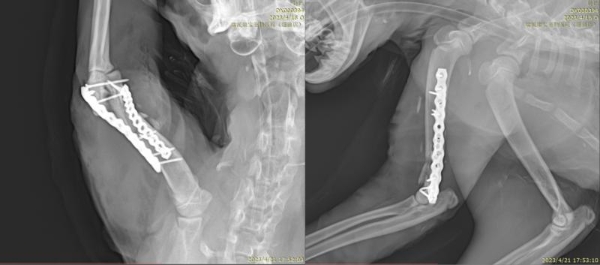

经系统影像学检查,刘玉龙医生确诊其为严重的双侧髋关节发育不良。考虑到患犬年龄小、病情重,若仅采取保守治疗或股骨头切除术,将无法逆转其进行性关节退化与功能障碍。在与主人充分沟通后,刘玉龙医生决定为其施行双侧髋关节置换术,从根本上重建髋关节结构与功能。

该病例的难点不仅在于患犬骨骼尚未完全发育成熟,手术精度要求极高;更在于双侧置换对手术规划、麻醉管理及术后康复都提出了系统性挑战。刘玉龙医生凭借丰富的关节外科经验,制定了分期手术方案,通过精确的假体选择与植入,成功恢复了患犬双侧髋关节的力学支撑与活动能力。术后患犬恢复顺利,运动功能显著改善,步态趋于正常,生活品质得到根本性提升。